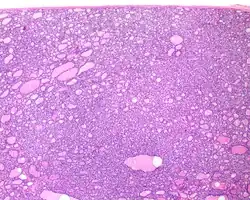

1) Encapsulated or partially encapsulated. The tumors are usually very well delimited or circumscribed, with the majority encapsulated, surrounded by a well formed fibrous connective tissue capsule.

3) Predominantly follicular pattern of growth. Papillary structures should not be present. Further, solid, insular, or trabecular architecture must be <30% of the overall tumor for this category to still apply. Colloid (the material that thyroid follicular cells create) is easily identified throughout.